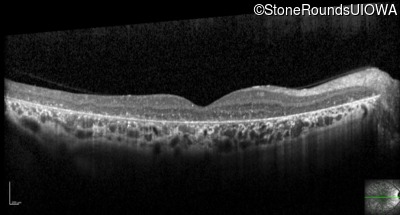

Optical Coherence Tomography - Right - 20/40 -1

Exemplar / OCT Stack

OCT Stack